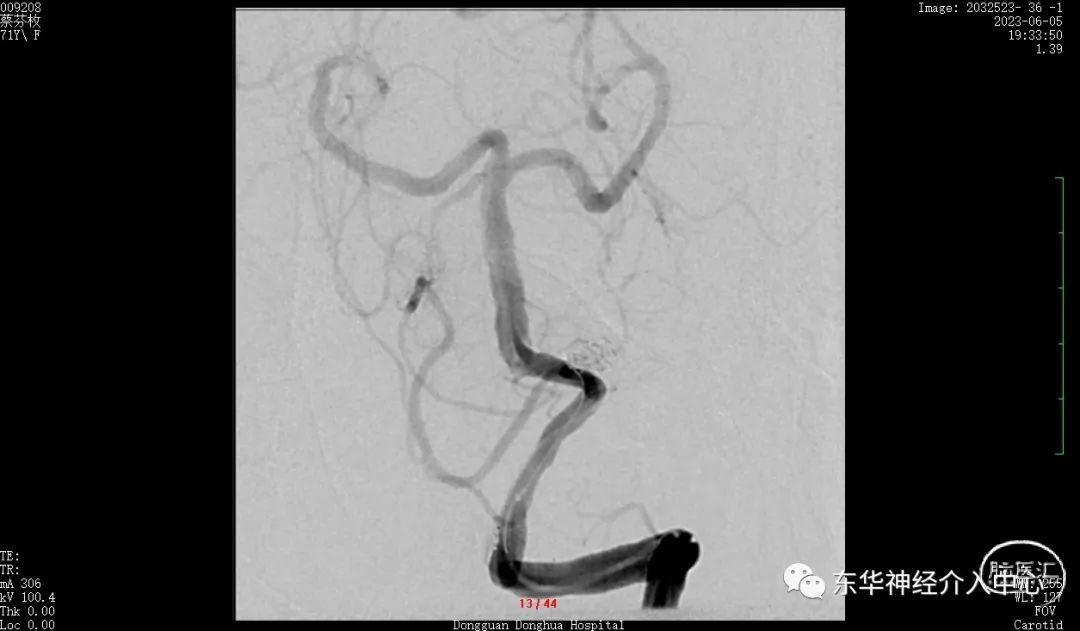

女性患者,高龄,68岁。突发头痛4小时入院。行头部CT+CTA 确诊为“自发性蛛网膜下腔出血,右侧PICA破裂动脉瘤 ”。家属选择介入治疗。术前根据CTA 的结果认为尽管动脉瘤是PICA 动脉瘤,但是应该是可以使用完成手术的,毕竟之前这个部位的动脉瘤也使用过支架辅助下成功手术过。尽管颈部CTA 提示同侧椎动脉开口狭窄、PICA 与椎动脉的夹角呈锐角,支架导管也是可以从对侧椎动脉翻山跨过双侧椎动脉汇合部到达PICA 内。手术尽管有难度但是应该可以完成的。如此信心满满的上手术台。但是造影后却郁闷了。发现手术难度大大的超过术前设想。

病人因为高龄、血管条件不好,到处硬化、斑块。同侧椎动脉开口狭窄,对侧椎动脉迂曲明显。PICA 从瘤颈发出。微导丝超选到位应该难度很大且风险极高。从对侧通过翻山越岭技术因为只有唯一的一根中间导管,所以只能硬着头皮从右侧椎动脉入路。

同侧椎动脉的开口狭窄,置入中间导管后血流不通畅。不得不进行开口的扩张。这倒是简单。扩张后顺利将中间导管置入合适位置。开始进行真正的动脉瘤栓塞术。